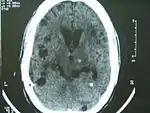

![]() МРТ пацієнта з нейроцистицеркозом, на якій видно множинні цистицерки у мозку. МРТ пацієнта з нейроцистицеркозом, на якій видно множинні цистицерки у мозку. | |

Рентгенологічно при нейроцистицеркозі виявляють множинні еліпсоподібні внутрішньочерепні кальцифікати різних розмірів, іноді аж до 7 см в діаметрі. Однак кальцифікація настає не раніше, ніж через 3 роки після зараження, а частіше ще пізніше — через 10 років і більше, але 97% хворих на цей час вже мають кальцифікати в скелетних м'язах. КТ, магнітно-резонансна томографія (МРТ) можуть виявляти некальцифіковані кисти, тому є діагностичними процедурами вибору. Вони на сьогодні адекватно замінили ті застарілі, нерідко громіздкі методи (ангіографія, ізотопне сканування, пневмоенцефалографія, вентрикулографія, мієлографія тощо), що колись широко використовували для діагностиці цистицеркозу.